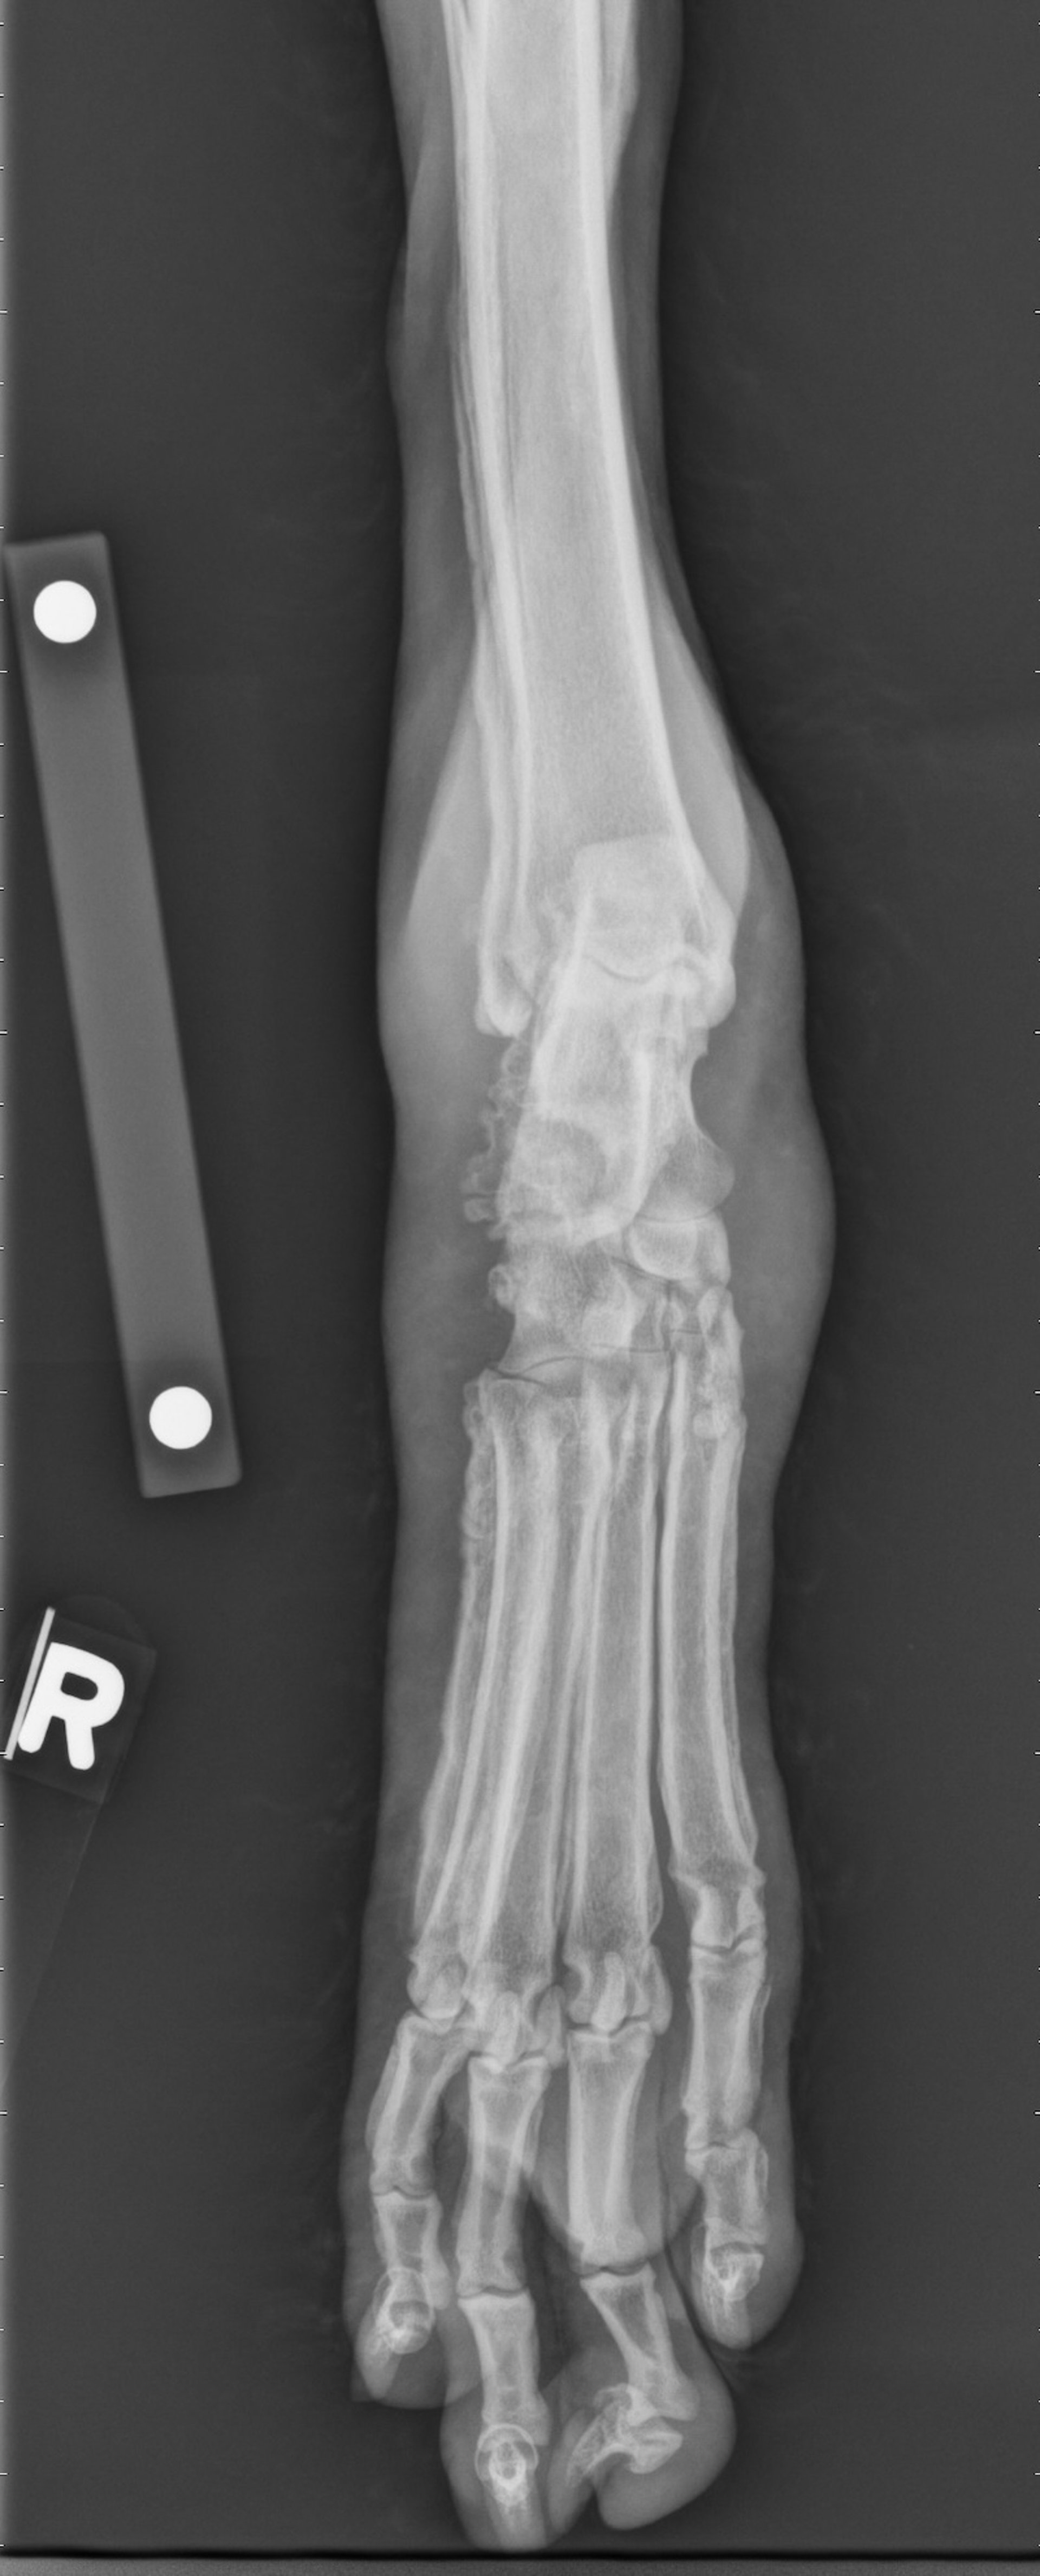

Hypertrophic osteopathy, radiograph, dog

Tarsal-metatarsal radiograph of a 16-year-old castrated male Miniature Poodle with hypertrophic osteopathy secondary to metastatic prostatic carcinoma. There is marked periosteal reaction along the margins of calcaneus, metatarsal bones, phalanges, and distal fibula. The periosteal reaction has a smooth to palisading appearance.

Courtesy of Dr. Po-Yen Chou.